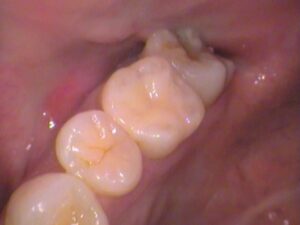

30代男性、検診で虫歯が見つかった患者さんです。

今回の場所は上の奥歯です。

今回は6番目の奥歯です。

歯を見てみましょう。

こちらの歯ですが、レジンの詰め物がされています。

赤枠で示した、ココですね!

よく見ると、

レジンが劣化したのか詰め物との間に隙間ができてきています。

歯との間に隙間ができています。

青く示している所です。